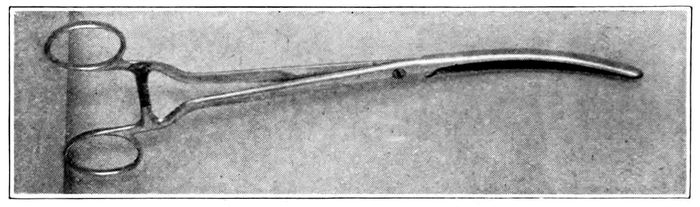

| 89. |

208 |

| 90. |

209 |